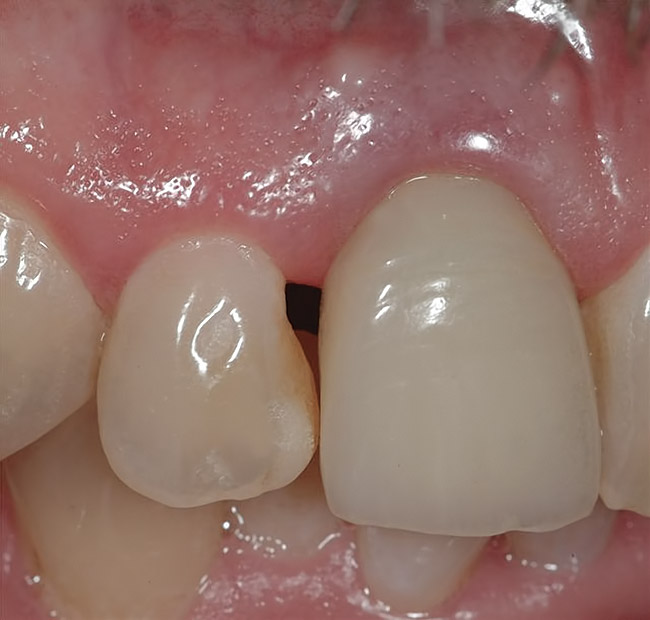

Figure 4  Characterization of the interproximal bone and tooth contacts: A periapical radiograph assists in measuring the distance from bone crest to the adjacent tooth contact points for missing tooth No. 8. The mesial bone crest to the adjacent tooth contact distance is < 5 mm, while the distal bone crest to adjacent tooth contact distance is > 6 mm (Fig 4). One-year following implant placement, conservation of these dimensions is revealed (Fig 5). The clinical photograph (Fig 6) of the lateral incisor adjacent to tooth No. 8 implant crown demonstrates that the absence of distal interproximal (papilla) fill related to the observed bone crest to contact distance exceeds 6 mm.

Figure 5  Characterization of the interproximal bone and tooth contacts: A periapical radiograph assists in measuring the distance from bone crest to the adjacent tooth contact points for missing tooth No. 8. The mesial bone crest to the adjacent tooth contact distance is < 5 mm, while the distal bone crest to adjacent tooth contact distance is > 6 mm (Fig 4). One-year following implant placement, conservation of these dimensions is revealed (Fig 5). The clinical photograph (Fig 6) of the lateral incisor adjacent to tooth No. 8 implant crown demonstrates that the absence of distal interproximal (papilla) fill related to the observed bone crest to contact distance exceeds 6 mm.

Figure 6  Characterization of the interproximal bone and tooth contacts: A periapical radiograph assists in measuring the distance from bone crest to the adjacent tooth contact points for missing tooth No. 8. The mesial bone crest to the adjacent tooth contact distance is < 5 mm, while the distal bone crest to adjacent tooth contact distance is > 6 mm (Fig 4). One-year following implant placement, conservation of these dimensions is revealed (Fig 5). The clinical photograph (Fig 6) of the lateral incisor adjacent to tooth No. 8 implant crown demonstrates that the absence of distal interproximal (papilla) fill related to the observed bone crest to contact distance exceeds 6 mm.